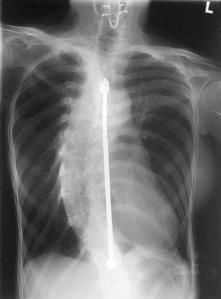

Scoliosis: Does it cause pain

Scoliosis is a common condition of the spine and I see it frequently in my practice. It is characterized by a curvature in the spine, usually from side to side. Although it is a complex three-dimensional deformity, on an X-ray, viewed from the rear, the spine of an individual with scoliosis may look more like an “S” or a “C” than a straight line. The amount of curvature can range from a barely noticable few degrees to nearly >70-80 degrees. Scoliosis is most often idiopathic (i.e. no-one knows what really causes it), but there are other types as well, that are [...]